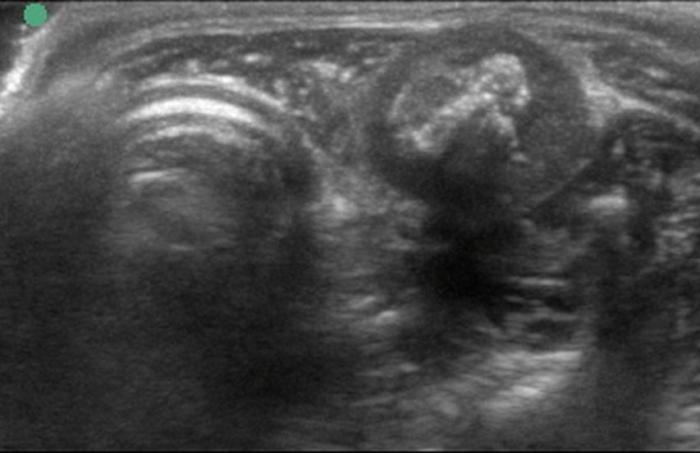

Respecto a las lesiones nodulares, la ecografía permite diferenciar nódulos sólidos, quísticos o mixtos (Figuras 8-10), y evaluar su tamaño, forma, ecogenicidad y comportamiento vascular. La presencia de nódulos hipoecogénicos, de contornos irregulares, con vascularización central intensa y crecimiento rápido, es sugestiva de neoplasia1.

Entre las neoplasias más frecuentes se encuentran los carcinomas tiroideos, los cuales suelen presentarse como masas lobuladas, de aspecto invasivo, con pérdida de la cápsula glandular, mineralización distrófica (ver Figura 8), desplazamiento o compresión de estructuras vecinas, y vascularización anómala al Doppler13 (Figura 11A-E).

La evaluación ecográfica permite, además, valorar la extensión local de la lesión, establecer sospechas de invasión a vasos o tejido peri tiroideo y guiar la toma de muestras por aspiración con aguja fina (FNA), especialmente en lesiones accesibles y sin compromiso de estructuras vasculares profundas11. No obstante, la ecografía tiene limitaciones en la diferenciación definitiva entre procesos inflamatorios y neoplásicos, por lo que siempre debe integrarse con estudios clínico-laboratoriales y citológicos18.